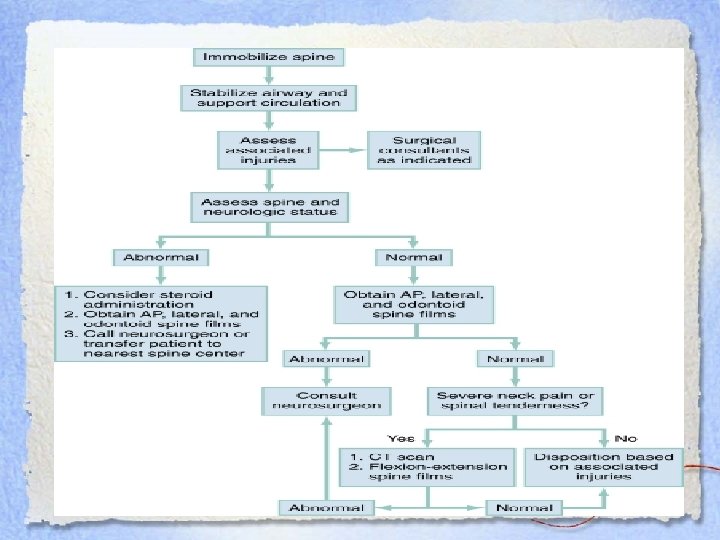

DI • C-spine films as per c-spine rules/nexus • CT • MRI: better for visualizing neurological, muscular and soft tissue – If CT negative and patient has positive neurological findings, this is next step – Important to image entire spine as 10% have 2 nd injury

DI • C-spine films as per c-spine rules/nexus • CT • MRI: better for visualizing neurological, muscular and soft tissue – If CT negative and patient has positive neurological findings, this is next step – Important to image entire spine as 10% have 2 nd injury

Treatment • • Prevent secondary injury Alleviate cord compression Establish spinal stability Assess the neurological deficit and spinal stability • Imaging • Consult spine/neurosurgery

Treatment • • Prevent secondary injury Alleviate cord compression Establish spinal stability Assess the neurological deficit and spinal stability • Imaging • Consult spine/neurosurgery